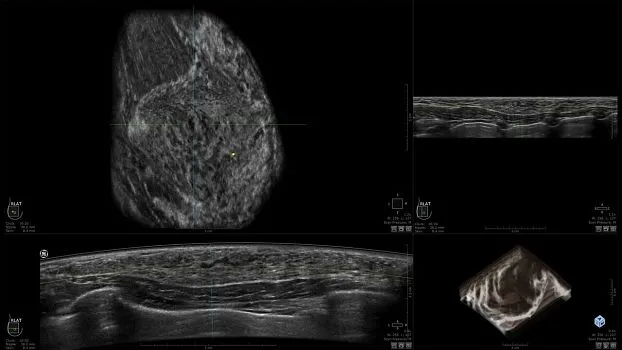

Клинические изображения

• Получение объемных 3D изображений с возможностью покадрового просмотра

• Получение изображений:

• Поперечная плоскость (в реальном времени)

• Коронарная плоскость (статическая, для указания нахождения соска)

• Отображение объемных 3D ультразвуковых изображений, которые состоят из традиционных поперечных и воссозданных коронарных и сагиттальных проекций

• Многооконный просмотр: 4 - 12 изображений.

• "толстый срез" в коронарной плоскости;

• поперечная;

• сагиттальная плоскость;